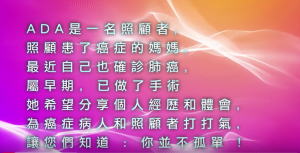

Clinical and Managerial Roles of Pharmacist in Cancer Care 詳情 肺癌患者分享治療經歷 詳情

肺癌患者分享治療經歷 詳情 流感疫苗該打唔該打? 流感疫苗該打唔該打? 詳情